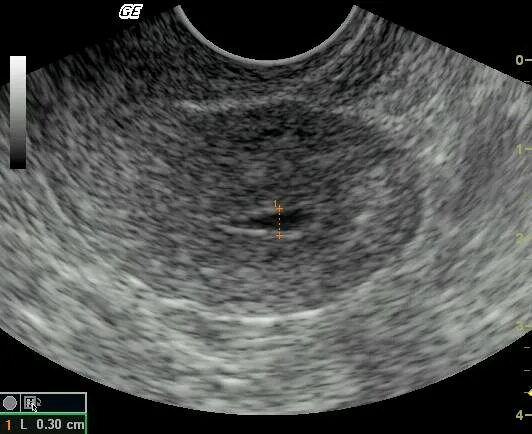

Расширен цервикальный